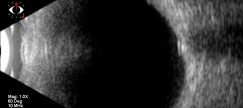

Ultrasonography

B-scan ultrasound can reveal an ovoid echogenic lesion at the junction of the retina and optic nerve. The degree of acoustic shadowing is proportional to the size of the echogenic focus. With papilledema, the intraorbital portion of the optic nerve is typically widened and will not decrease in width with prolonged lateral gaze (30 degree test). Drusen do not produce widening of the intraorbital nerve. This imaging method is advantageous because it can scan the entire area of the optic disc to show posterior borders of deep, calcified drusen. However, this method has poor resolution of the drusen and can miss uncalcified, buried drusen.